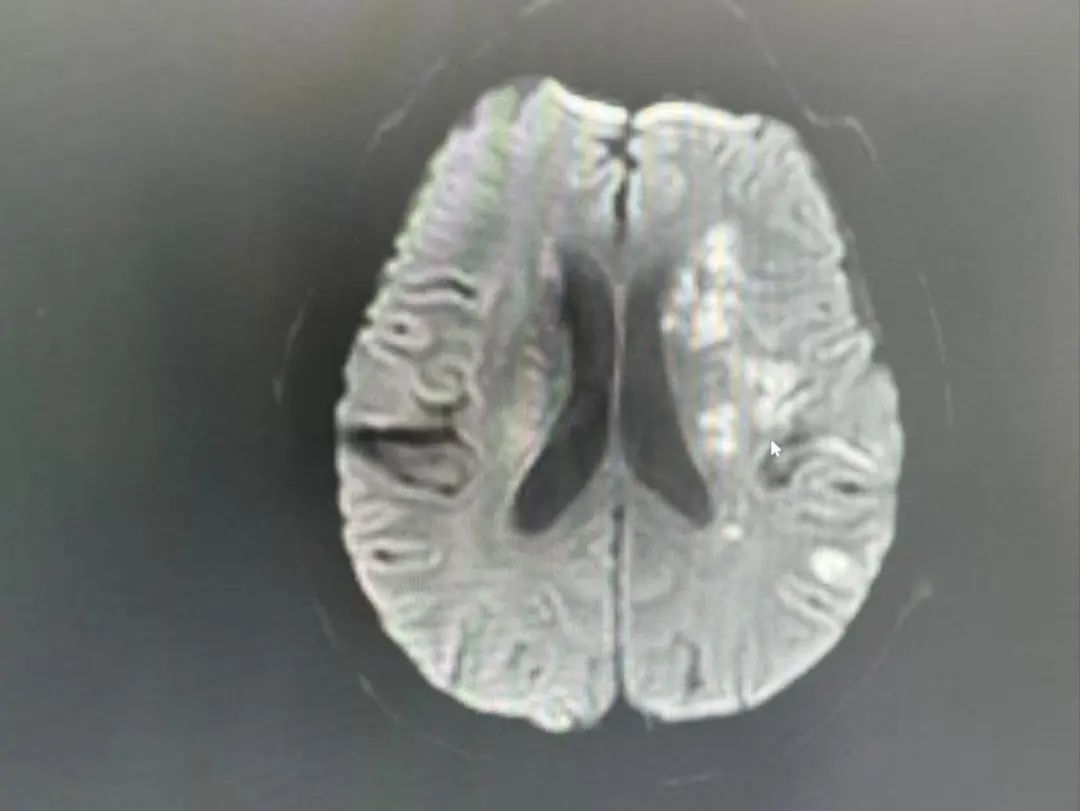

"左侧大脑中动脉闭塞!"

头颈部CTA检查揭开了更凶险的真相:

多发性脑梗死:左侧大脑关键区域受损

血管危机:左侧大脑中动脉闭塞,血流几乎中断

罕见盗血现象:锁骨下动脉重度狭窄,导致血流“偷走”了脑部的供血